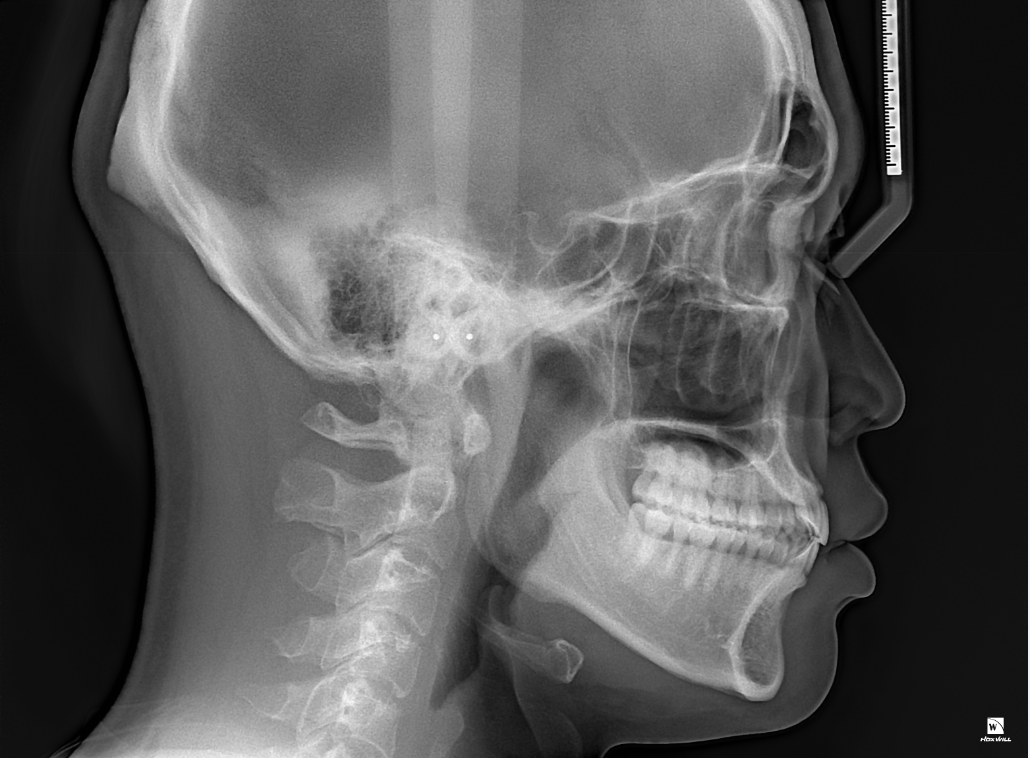

사진상으로 보았을 때는 치축의 각도가 정상 범주에서 벗어나는 것이 맞습니다. 다만 치열이 고르고 특별히 불편감이 없다면 치료의 대상은 아닙니다. 오히려 현재 골격에서 아래 위 치아의 치열 각도를 바꾸게 되면 심미적으로 더 이상해보일 수 있으므로 정확한 교정적 평가 이후에 교정을 하는 것이 필요하며 교정 이후에 오히려 어색해보일 수도 있어 보입니다.

이상적인 피개교합은 2mm입니다.

하지만 사람에 따라 조금씩 다를 수는 있기때문에

자세한 검사를 받아보시는 것을 추천드립니다.